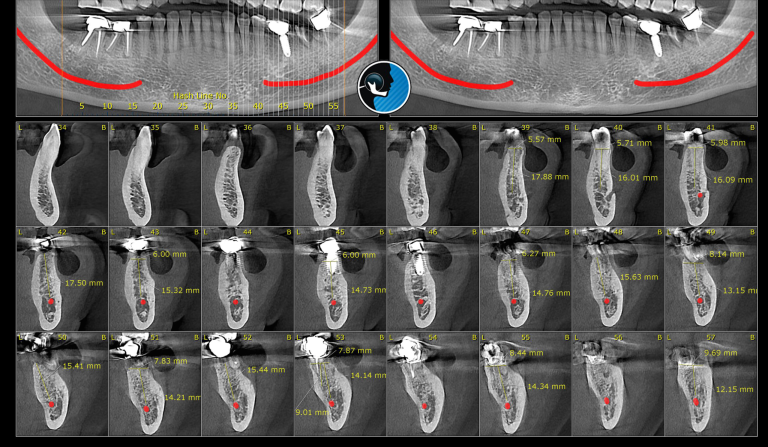

CBCT استخوان فک: انقلابی در تصویربرداری دندانپزشکی و جراحی فک و صورت در دنیای مدرن دندانپزشکی و جراحی فک و صورت، فناوری نقش اساسی در تشخیص دقیق و ارائه درمانهای موثر ایفا میکند. یکی از پیشرفتهترین ابزارهای تصویربرداری که در…